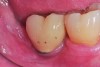

Fig 6. At 1 year following treatment, probing depths are now 3 mm with an absence of bleeding.

Figure 6